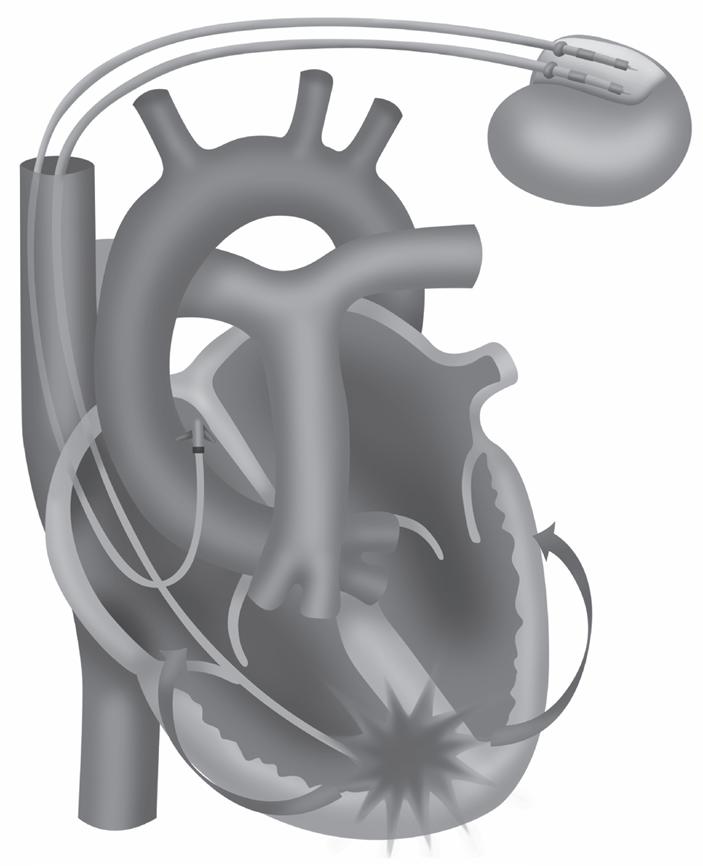

15 Marca-passo Provisório, Definitivo, Ressincronizadores e Desfibriladores, 145 Julianny Freitas Rafael Magacho • Vicente de Paulo Fernandes do Nascimento • Amanda Mendonça da Silva Costa • Nathália Rodrigues da Silva • Gustavo Luiz Gouvêa de Almeida Jr.